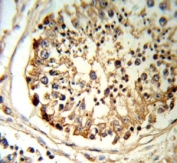

tPA antibody IHC analysis in formalin fixed and paraffin embedded human testis tissue.